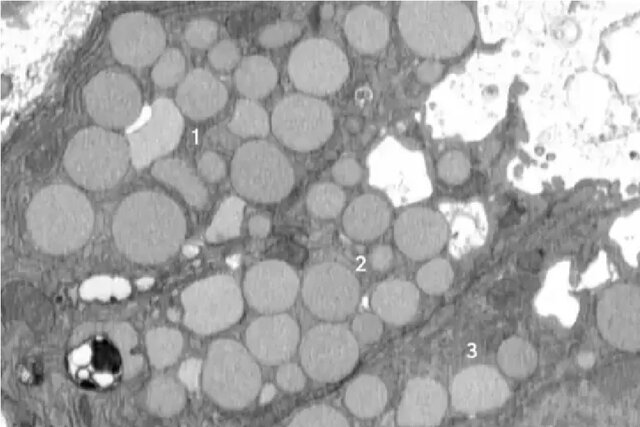

دکتر براون در طول تحقیقات مداوم خود متوجه وجود بقایایی در خارج از سلول‌ها در یک مدل آسیب معده در موش‌ها شد. او متوجه شد که با ادامه پخش شدن مواد زائد، اتفاقی عمدی در حال رخ دادن است. آسیب معده این اثر پاکسازی یا کاتارتوسیتوز را در پاسخ ترمیمی بزرگتر پالیژنوز ایجاد کرد. این زمانی است که یک سلول برای بهبودی به حالت سلول بنیادی برمی‌گردد.

اساساً سلول‌ها برای پاکسازی دستگاه سلولی خود، مواد زائد را استفراغ یا پاکسازی می‌کنند. این به عنوان یک میانبر عمل می‌کند که به آنها اجازه می‌دهد بافت سالم را سریع‌تر رشد دهند، زیرا روش معمول آنها برای تجزیه مواد زائد خیلی طول می‌کشد. با این حال، این عمل دارای معایبی است.

سلول‌ها راه‌های متعددی برای تقویت التیام دارند، اما این حالت تازه شناسایی شده به سلول‌ها اجازه می‌دهد تا اجزای قدیمی را از بین ببرند و دوباره نو شوند که به آنها کمک می‌کند بافت سالم را بازسازی کنند. به گفته نویسندگان این مطالعه، این روش به نحوی است که انگار سلول‌ها استفراغ می‌کنند.

«کاتارتوسیتوز» اولین بار در سال ۲۰۱۸ توسط دکتر جیسون سی. میلز (Jason C. Mills)، نویسنده ارشد همین مطالعه توصیف شد. این فرآیند بخشی از یک پاسخ ترمیمی بزرگتر به آسیب به نام پالیژنوز (paligenosis) است که در آن سلول‌ها خود را برای بازگشت به حالت «نابالغ» یا جوان، دوباره برنامه‌ریزی می‌کنند.